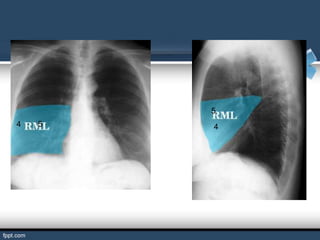

BRONQUIOS LOBARES

El bronquio principal derecho se divide en los llamados bronquios

lobares (son tres: superior, medio e inferior). El bronquio principal

izquierdo se divide a su vez en bronquios lobares (son dos: superior

e inferior).

Los bronquios lobares derecho e izquierdo se subdividen a su vez en

bronquios segmentarios o terciarios por cada lado.

BRONQUIOS SEGMENTARIOS

Son ramificaciones de los bronquios lobulares.

El hombre tiene 18 bronquios segmentarios que estos se ramifican

en bronquiolos.

Si los bronquios segmentarios ya no se puede subdividir se le llama

bronquiolo terminal.

5

4   5   4

6

4

4           5